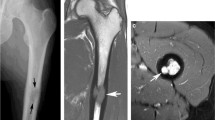

A 1.5 Tesla whole-body MRI (Siemens Avanto Fit, Siemens Healthineers, Erlangen, Germany) was performed to investigate the detected osteolytic lesions and potential differential diagnoses like metastases and plasma cell dyscrasias. The protocol consisted of whole-body coronal T1- and T2-STIR-weighted images and sagittal T1-weighted, T2-weighted with fat saturation and contrast-enhanced T1-weighted images with fat saturation, DWI, and DCE-MRI of the thoracic and lumbar spine and sacrum (Table 1). Focal bone marrow lesions were detected in the entire axial and appendicular skeleton, except for the left scapula [7] (Fig. 3). The lesions’ diameters varied from 3 mm (left humerus) to 63 mm (right posterior iliac bone). Other extensive lesions were detected in the distal lateral metaphysis of the right femur (52 mm), the right lesser trochanter (41 mm), the right scapula (33 mm), the right humerus (20 mm), the posterior aspect of the left seventh rib (10 mm) and the mandible (9 mm). They were characterized by a low signal intensity (SI) on T1-weighted images and an intermediate to high SI on T2-weighted images with fat saturation and extensive enhancement. Furthermore, the lesions were inhomogeneous with irregular borders and showed central fat inclusions. These changes were visible both on the coronal and the sagittal images. The bone marrow surrounding the lesions in the spine and elsewhere in the skeleton appeared normal. The lesions presented with diffusion restriction on the DWI sequences (Fig. 4b, c) and showed highly increased vascularization and perfusion on DCE-MRI (Fig. 4d). The surrounding bone marrow showed no diffusion restriction and normal, slow time-intensity curves [8]. No increased vascularization and perfusion were noted.

Whole-body MRI examination with T1-weighted (upper row) and T2-weighted images after fat saturation (lower row). a, d Coronal images show a large T1 hypo- and T2-STIR hyperintense lesion of the right iliac bone with irregular borders (arrow). b, e Coronal images show a large T1 hypo- and T2-STIR hyperintense lesion of the distal right femur with irregular borders (arrow). c, f Sagittal images show two large T1 hypo- and T2-STIR hyperintense lesions of the L3 and S3 vertebral bodies (arrows)

A bone biopsy of the right posterior superior iliac spine was conducted to investigate one of the detected bone lesions suspected for malignancy (Fig. 5). The bone marrow could be investigated for a variety of differential diagnoses like MM, Langerhans cell histiocytosis or lymphoma at the same time. A control CT pelvis was conducted to evaluate the biopsy trajectory and rule out possible sampling error.

Trephine biopsy of the iliac crest. a At low magnification, mainly fibrosis is visible (hematoxylin and eosin, × 100). b In this case, even at high magnification, individual histiocytes are more difficult to recognize than usually in ECD, due to important fibrosis. The background shows barely discernible histiocytes with delicate vacuolization (hematoxylin and eosin, × 400). c At immunohistochemical staining for CD68, the histiocytes become clearly visible (hematoxylin and eosin, × 200)

The biopsy underwent decalcification prior to microscopic investigation. Bone trabeculae interspersed with hematopoietic tissue were evident. The bone marrow had a normal cellularity. All hematopoietic lineages were well represented and showed normal maturation. Several large areas of fibrosis were present in the bone marrow, which demonstrated focal lymphocytic infiltrates and scattered plasma cells. At high magnification, some histiocytes with ill-defined vacuolated cytoplasm could be discerned in the areas of fibrosis. Immunohistochemistry (IHC) of the lymphoid infiltrates showed both CD3 and CD20 positivities, indicating the presence of both B- and T-lymphocytes. No atypical lymphocytes could be identified. IHC for CD138 confirmed increased plasma cells, polytypical for kappa and lambda light chains. In MM, a monoclonal expansion of kappa or lambda plasma cells would be expected [10]. Plasma cells were mainly positive for IgG without increase of IgG4-expressing cells, indicating the lesions were not caused by IgG4-related disease. No aberrant expression of cytokeratins or CD30 was seen, excluding metastatic malignant epithelial cells and anaplastic large cell or Hodgkin lymphoma, respectively. IHC for CD68 demonstrated multiple histiocytes. These did not stain for CD1 and langerin, excluding Langerhans cell histiocytosis [5]. A slight increase of mast cells was noted in the fibrotic areas by IHC for CD117 and mast cell tryptase. There was, however, no cluster formation and the mast cells showed normal morphology, making the diagnosis of a mast cell tumor unlikely. ALK, HMB45 and S100 IHC were negative, making the diagnosis of anaplastic large cell lymphoma and melanoma unlikely as well. Additionally, S100 negativity again pointed toward ECD, as this is usually positive in a Langerhans cell histiocytosis [5]. The blood vessels were ERG-, CD34- and CD31-positive, indicating normal presence of endothelial cells and possible endothelial progenitors caused by angiogenesis.